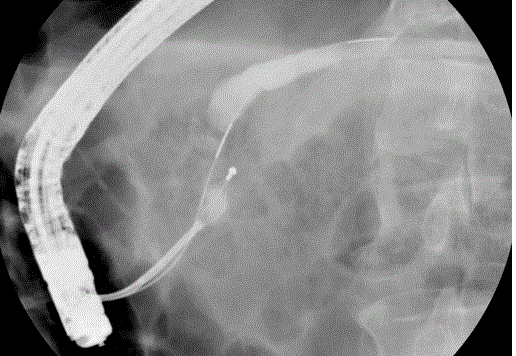

Figure 1. Basket impaction of pancreatic duct stone during mechanical lithotripsy.